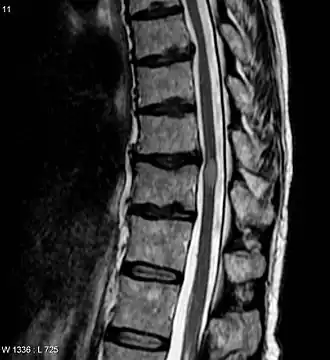

MRI met myelitis transversa (lichte, ovale vorm midden rechts. De patient herstelde 3 maanden later.